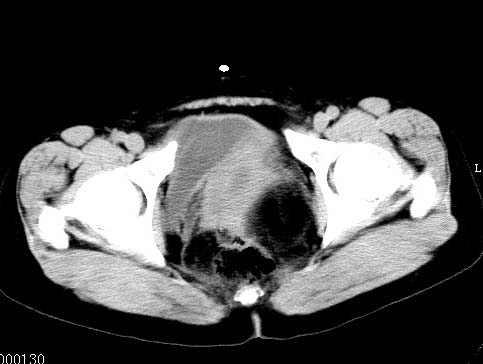

女性 病人 44岁 盆腔 下腹部痛1天!

盆腔内低密度为主混杂等密度及少许囊样与班状钙化影,如果做了肠道准备就好了。支持畸胎瘤。当然做mri会更好

典型的双侧附件畸胎瘤.

支持各位大侠观点.病人有急性腹痛,需除外有扭转可能.建议mri.

盆腔多发畸胎瘤,较为典型。